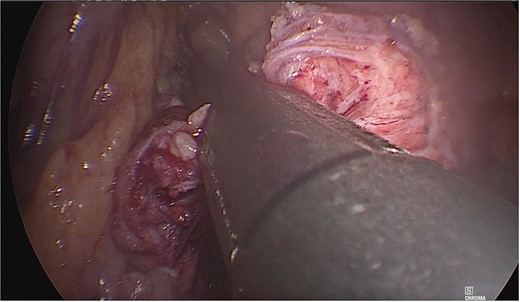

A tumor measuring ~1.5 × 2 cm was identified at the junction of the body with the tail of the pancreas, and dissection of the mesenteric vessels and portal vein was continued. Subsequently, the splenic vein and artery were dissected from the medial to lateral direction at a distance of 2–3 cm. Once released, the neck of the pancreas was divided with an Endo GIA 60 mm endoscopic stapling device (Fig. 3), and a second stapling was performed with an Endo GIA 45 mm (Fig. 4).

The neck of the pancreas was divided using an Endo GIA 60 mm endoscopic stapling device.